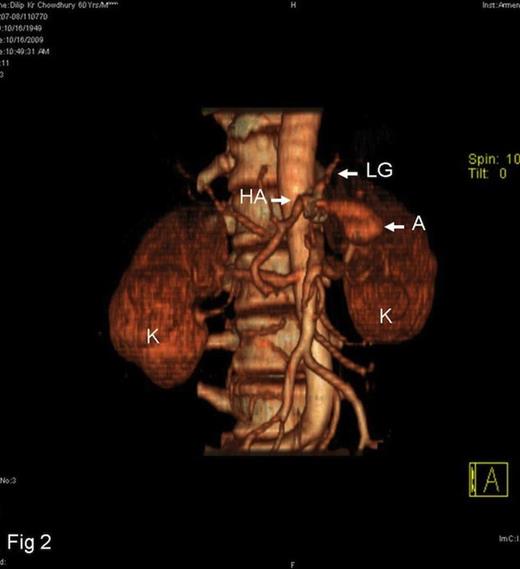

A 60-year-old male was referred with history of repeated epigastric pain and malena. The pain was intense, radiated to the back and, on occasion was associated with profuse sweating and fainting attacks. In the preceding four months, he had 5 such episodes of pain and malena. These attacks were characterized by malena occurring a few hours after the onset of pain and were associated with transient elevation of serum amylase and lipase. He was a known hypertensive on regular medicines and denied any history of alcohol consumption. During the last episode of bleeding, his hemoglobin had dropped to 3.5gms/dl requiring 8 units of blood transfusion. Upper GI endoscopy performed on three occasions showed bleeding from the second part of the duodenum, but the source of bleeding remained obscured. Colonoscopy at the time was unremarkable. In view of suspected pancreatitis, abdominal ultrasonography was performed, which revealed a hypo-echoic lesion near the head-neck junction of pancreas. On contrast CT scan, this lesion turned out to be a partially thrombosed 7cm aneurysm close to an otherwise normal pancreas (Fig.1). The 3D-CT reconstruction clearly demonstrated the origin of the aneurysm to be from the splenic artery (Fig.2). To stem further bleeding, a coeliac axis angiography followed by micro-coil embolisation of splenic artery was performed.

3D-CT reconstruction of the aneurysm ( HA =hepatic artery, LG =left gastric artery, A =aneurysm, K =kidney)